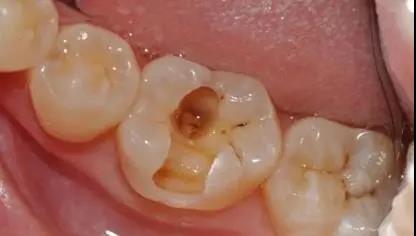

▶ 被“蛀出洞”的牙齿

其中,咬颌龋是发生在牙齿的咀嚼面,也就是牙齿表面最宽、咀嚼食物的那一面,我们最常见到的蛀牙就是咬颌龋。

至于邻面龋,顾名思义,它是发生在牙齿与牙齿对接的相邻面,也就是牙缝中,由于它是在“夹缝中生存”,潜伏性很强,所以没有发展到比较严重的时候是难以发现的。

牙齿邻接处缺损,出现龋洞